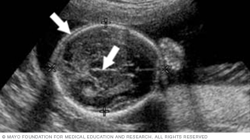

The image below shows all four chambers of the heart, as well as the heart valves. This type of image usually is taken during an ultrasound done between weeks 18 and 22 of pregnancy. Fetal ultrasound is used to check that the heart is working properly and to see if there could be any heart problems.